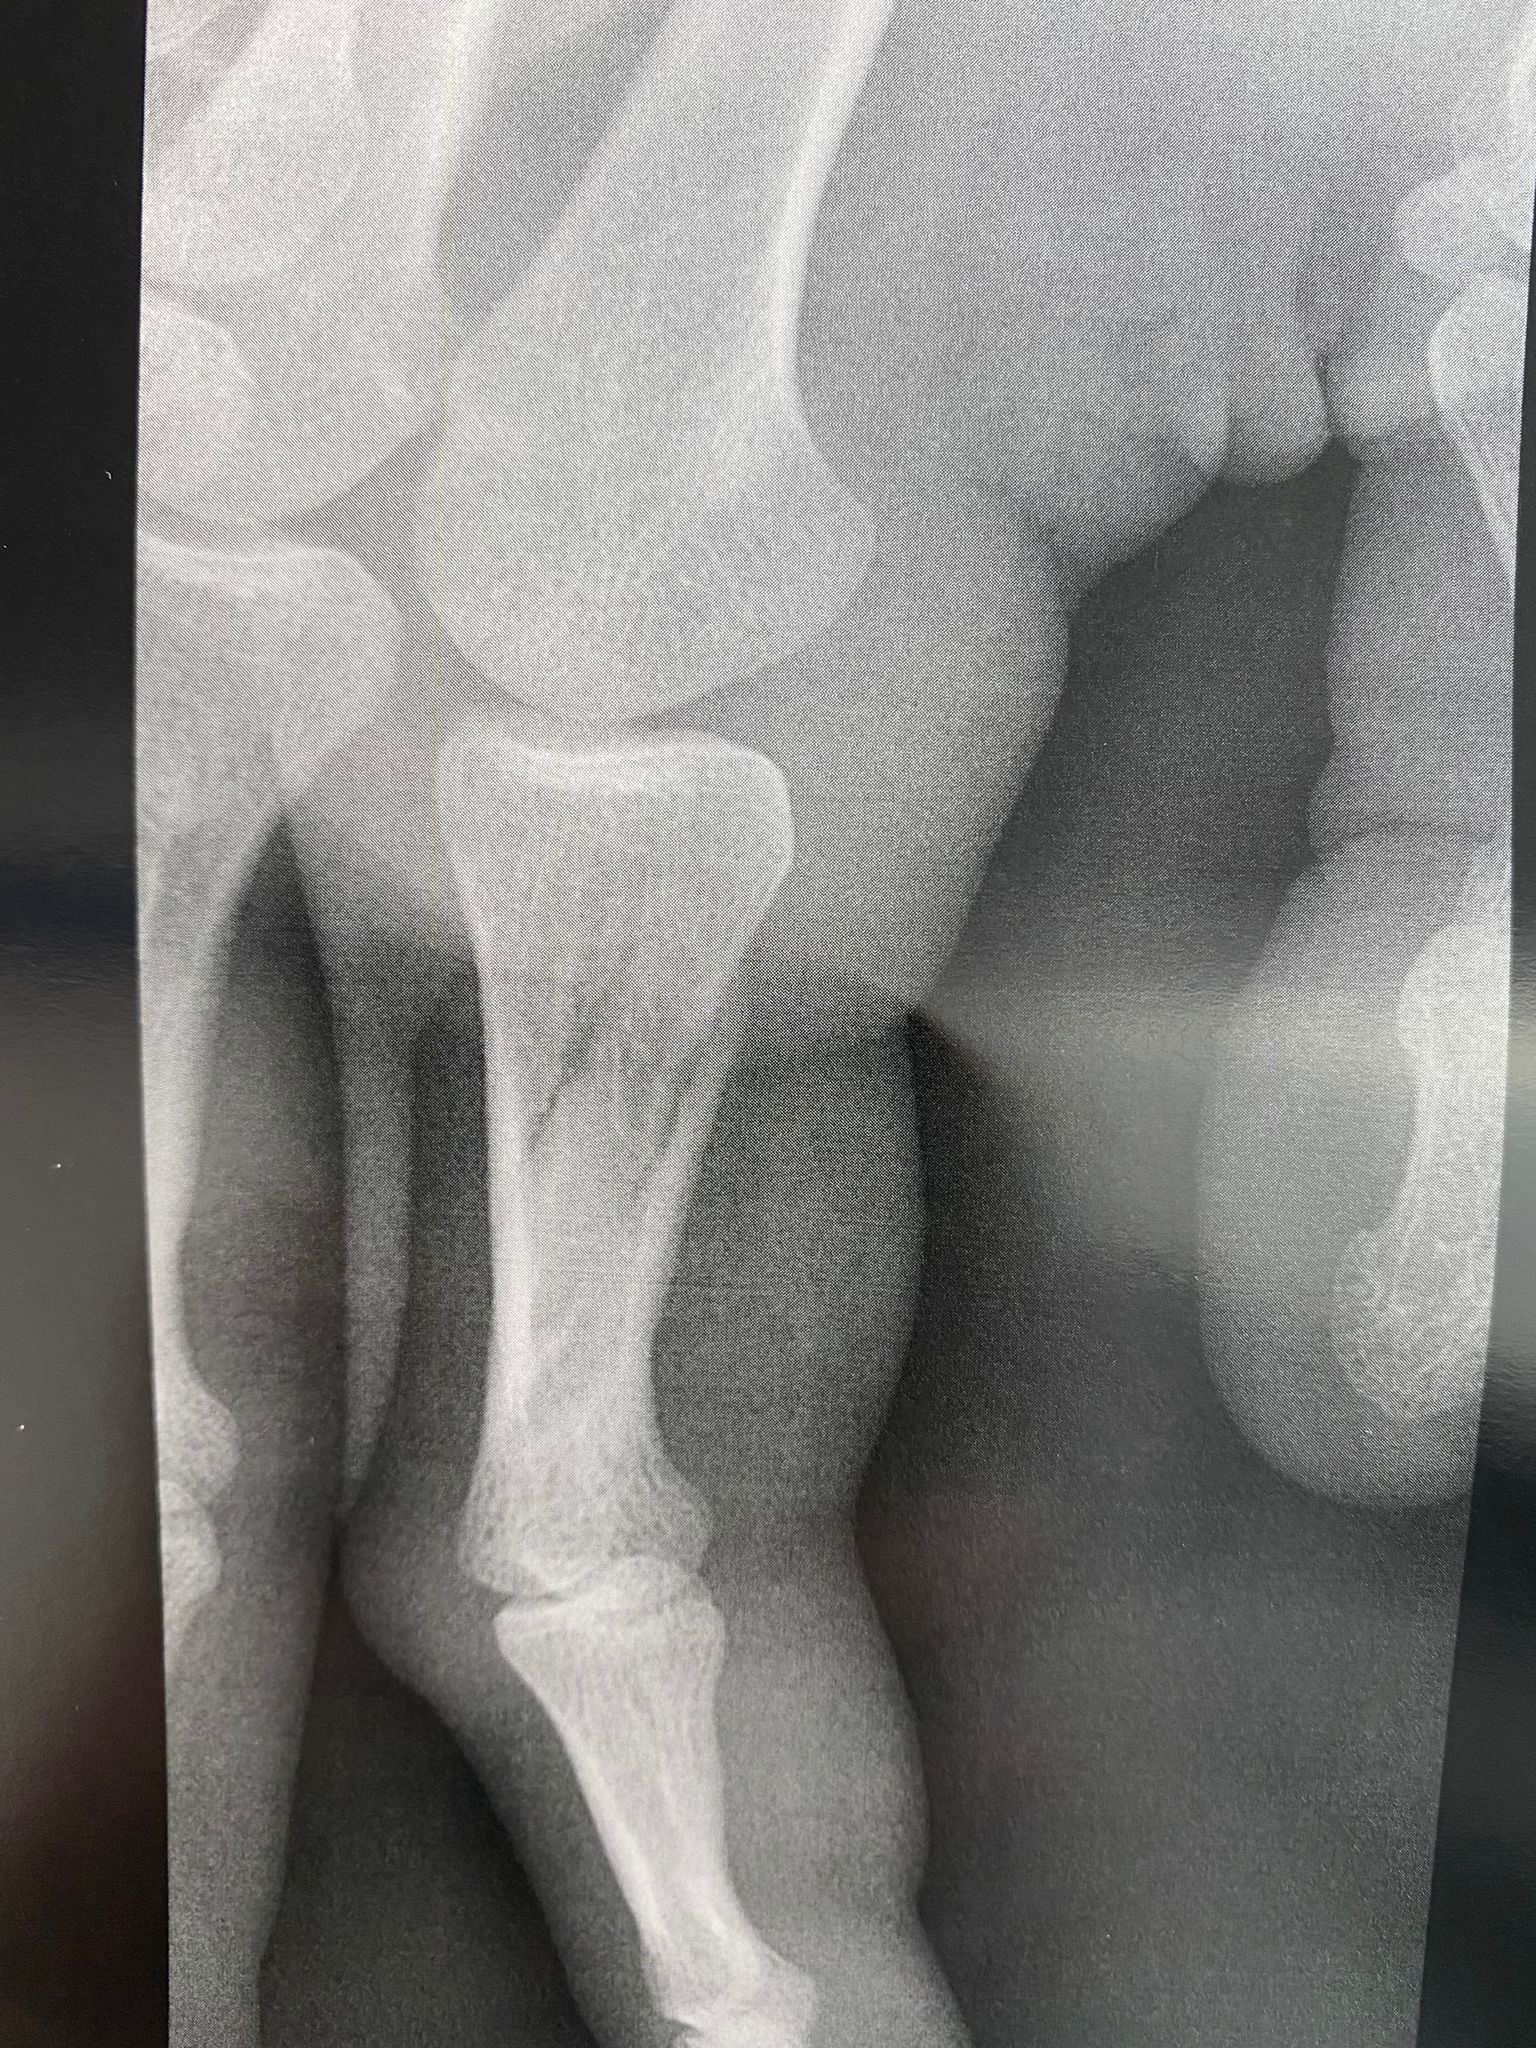

Kapiten košarkaške reprezentacije Bosne i Hercegovine Miralem Halilović doživio je tešku povredu u utakmici francuskog kupa.

Poslije samo četiri minuta igre u kup utakmici između Orelansa i Nanterrea Miralem Halilović je slomio prst. Teška povreda će bh. reprezentativca udaljiti sa parketa prema prvim pognozama najamanje do kraja 2022. godine.

Povreda kapitena Zmajeva je teže prirode, a u foto galeriji koja se nalazi u prilogu možete pogledati trenutni izgled prsta košarkaša Nanterrea.